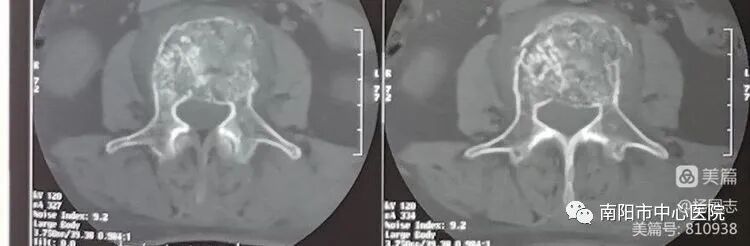

腰3椎體骨質(zhì)破壞,轉(zhuǎn)移癌,單發(fā)椎體骨質(zhì)破壞,寡病灶